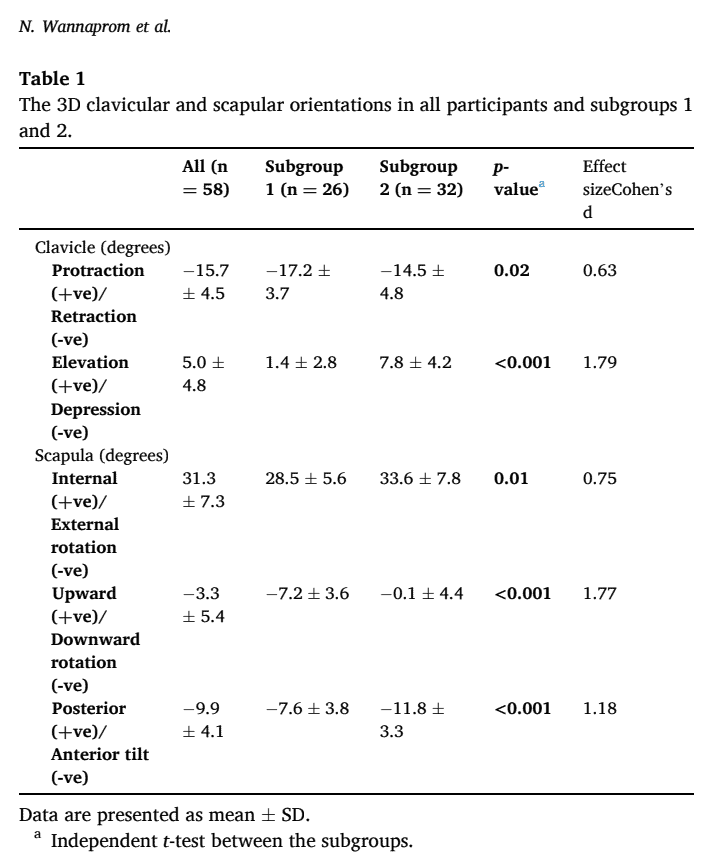

Hai nhóm nhỏ được xác định dựa trên phép đo 3D. Ở nhóm phụ 1, những người tham gia biểu hiện co xương đòn và xoay xương bả vai xuống dưới nhiều hơn. Ở nhóm phụ 2, độ cao của xương đòn tăng lên và xương bả vai nghiêng về phía trước nhiều hơn và xoay vào trong nhiều hơn. Nhóm 1 có báo cáo thường xuyên hơn về tình trạng đau đầu và đau nhiều hơn ở vùng cổ trên hoặc toàn bộ cổ, trong khi những người ở nhóm 2 báo cáo đau nhiều hơn ở vùng cổ dưới. Đối với tất cả các kết quả khác (nhân khẩu học, cường độ đau cổ, thời gian kéo dài và tình trạng khuyết tật), các nhóm con đều như nhau.